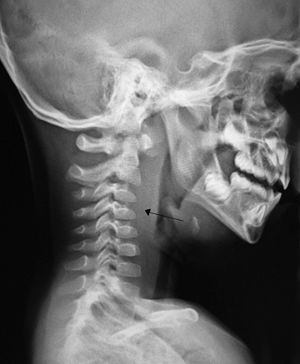

Criança com quadro recente de IVAS, passa a apresentar…

Qual o diagnóstico?

Qual a conduta?

ABSCESSO RETROFARÍNGEO

(Adenite dos gânglios retrofaríngeos; crianças < 5a)

INTERNAÇÃO HOSPITALAR